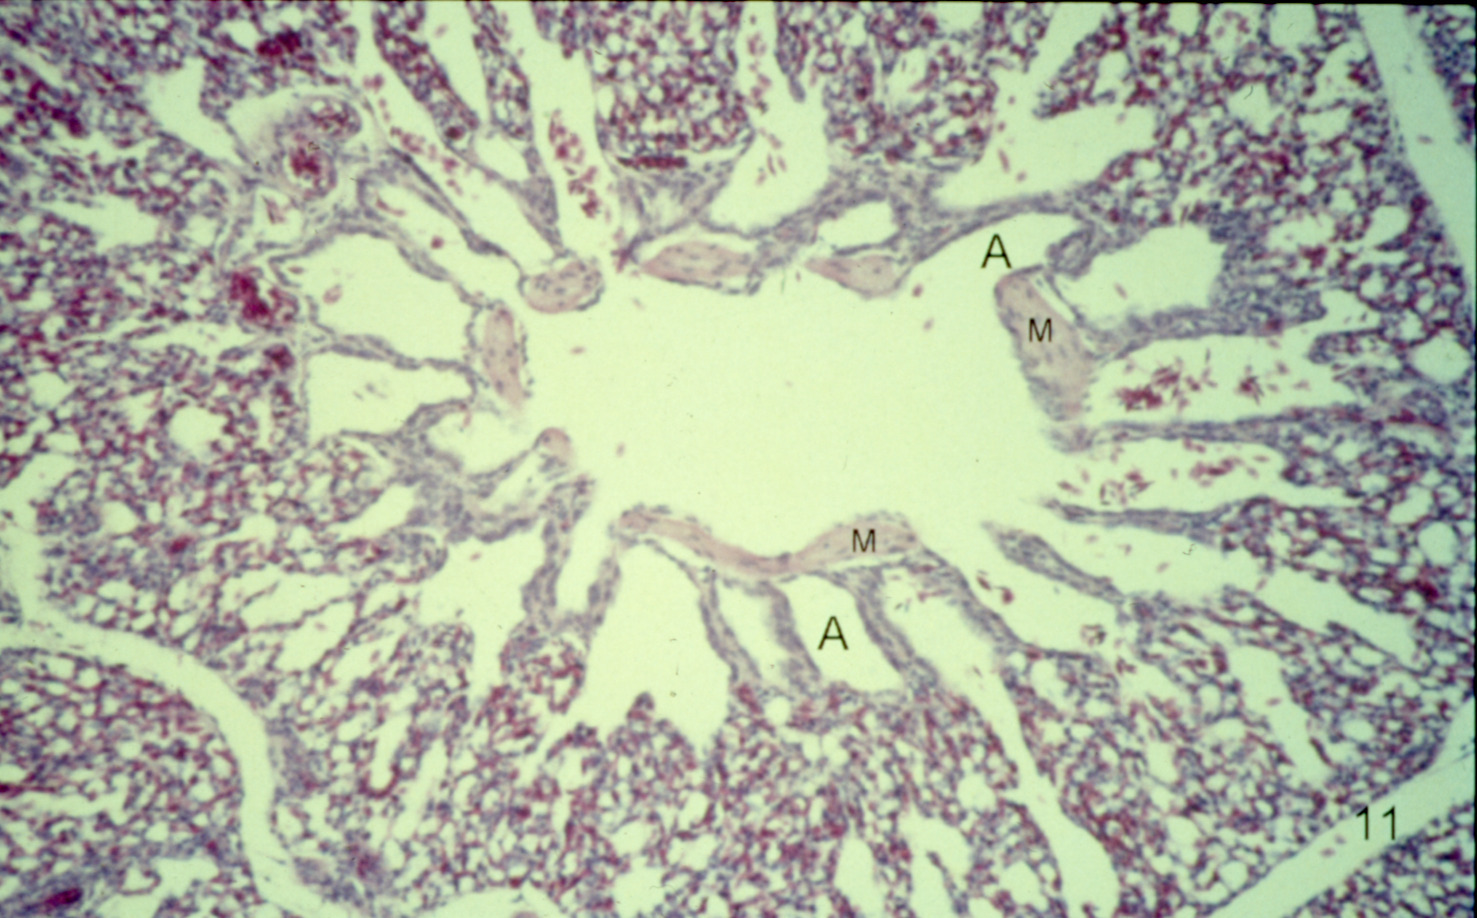

Ascites syndrome in meat-type chickens (slide study set no. 23)

Chickens--Diseases Ascites

Slide Study Set #23, Ascites Syndrome in Meat-Type Chickens (includes 27 color slides), 2001